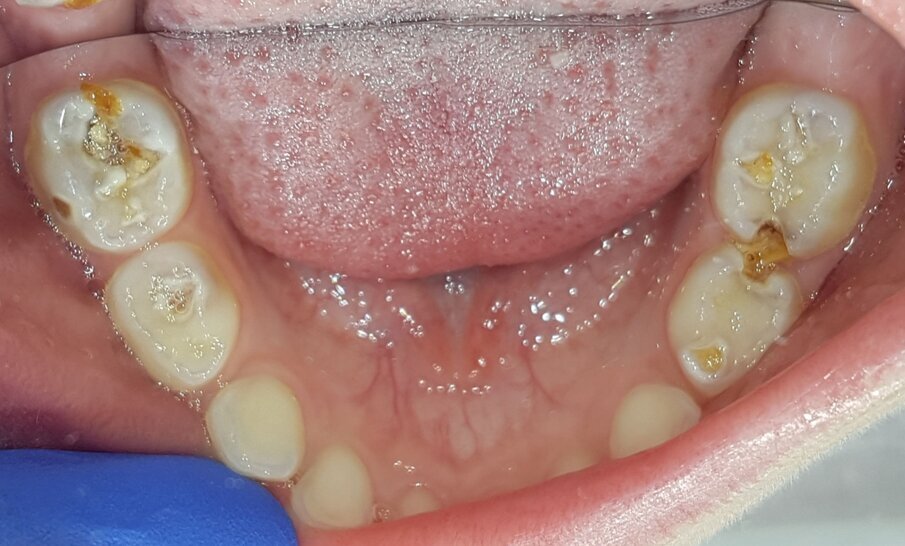

Een kind van vierenhalf jaar met multi-cariës werd verwezen voor behandeling onder narcose (afb. 6a-e). Klacht: lichte gevoeligheid .

Afbeelding 6a. Multi-cariës bij intake.

Afbeelding 6b. Multi-cariës bij intake.

Afbeelding 6c. Multi-cariës bij intake.